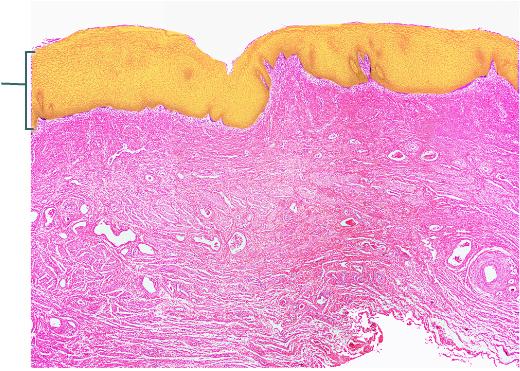

Identify the highlighted tissue in the vaginal wall.

Stratified Squamous Epithelium